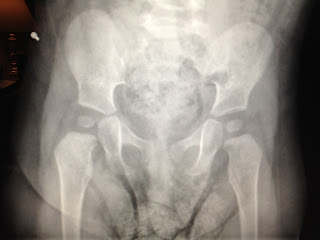

Sister has her appointment in December, but since she was with Dr. England took a peak at her progress. I mentioned my concerns about how flexible her hips are... this girl is out of control! He noted a "click" at about 45-60 degrees and suggested we get an x-ray done just to make sure her socket is perfect. We had time today, so we got it done right away. She's looking great! Kind of a fun little Halloween souvenir too. Having clubbed feet and being a girl just makes her predisposed to being extra flexible I guess. Olympics here we come!